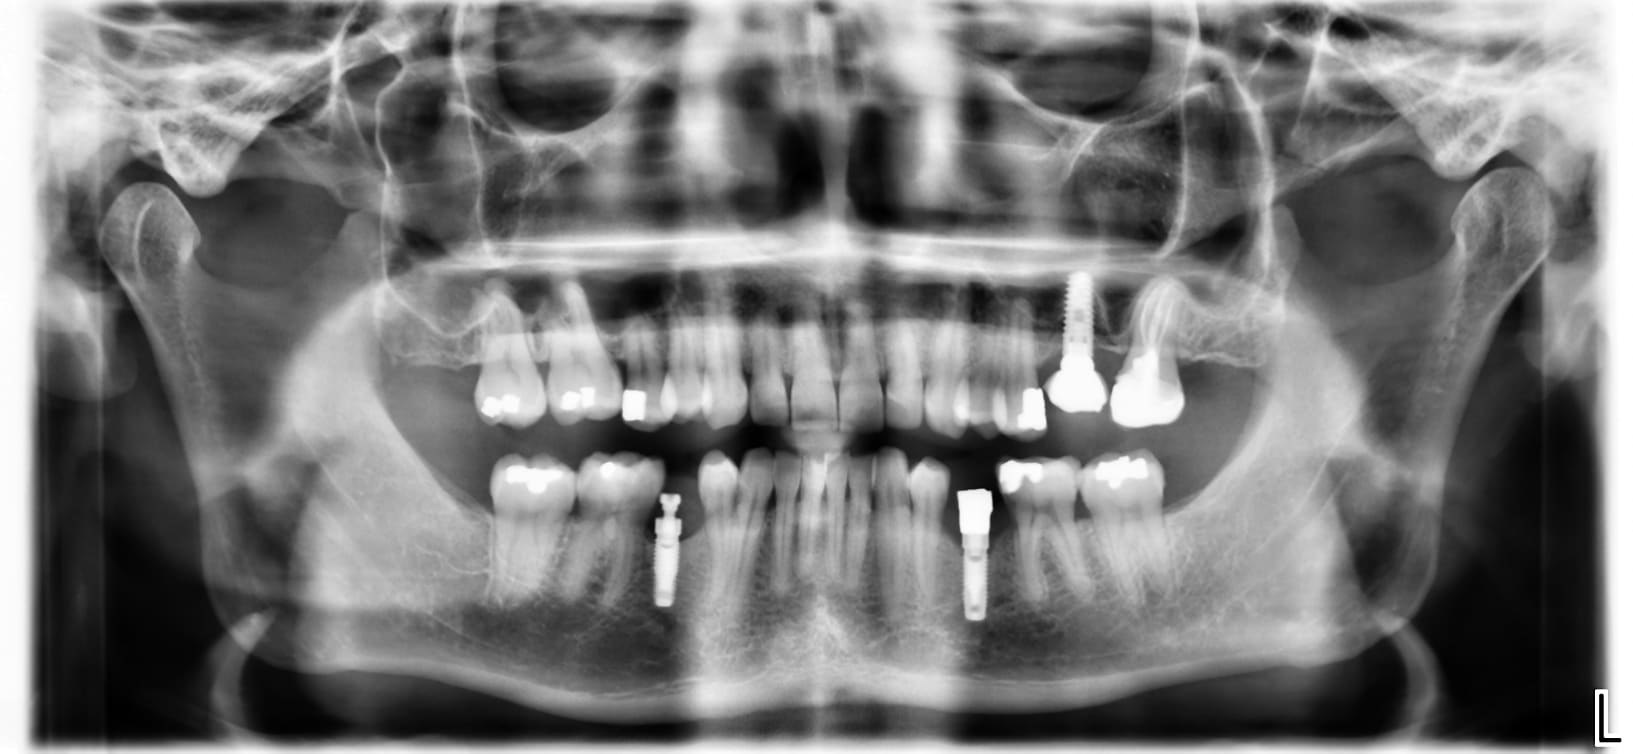

Bonjour à tous, qui peut me dire de quelle marque sont les différents implants de cette radio ?

oui désolé... c'est mieux? plutôt Nobel la 35 non ?

première radio: Sterioss

les 2 autres photos (du même implant)....çà ressemble à du MIS Lance ou similaire....pour moi la connexion doit être un standard "Zimmer"....